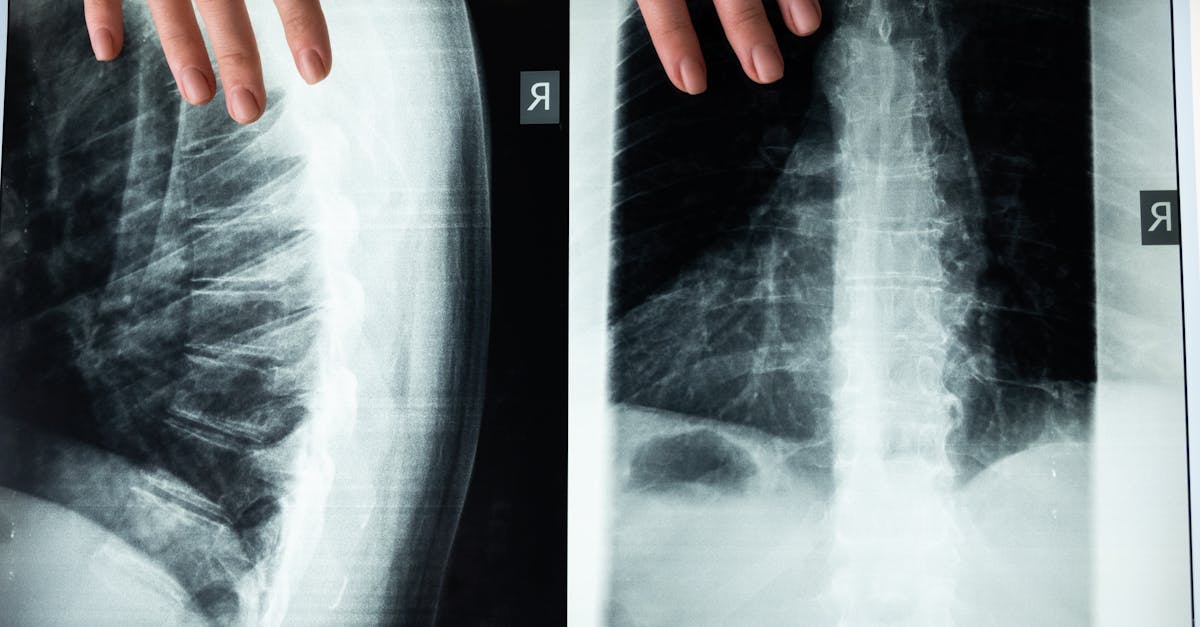

Imagerie médicale

Le diagnostic est souvent confirmé par des techniques d’imagerie médicale telles que les rayons X ou l’IRM. Ces examens révèlent des anomalies anatomiques dans la colonne vertébrale, comme le rétrécissement du canal rachidien. Ils permettent d’observer non seulement l’alignement de la colonne vertébrale, mais aussi l’état des disques intervertébraux et des articulations.

Pour confirmer le diagnostic, des techniques d’imagerie telles que les radiographies, l’imagerie par résonance magnétique (IRM) ou les tomodensitométries peuvent être requises. Ces examens permettent de visualiser les structures osseuses et les tissus environnants, aidant ainsi à détecter des anomalies telles que des hernies discales ou un rétrécissement du canal spinal. L’IRM est souvent privilégiée car elle fournit une vue détaillée des nerfs et des tissus mous, essentielle pour un diagnostic précis.

En cas de suspicion de sténose spinale, le clinicien peut recommander des examens d’imagerie. Les techniques comme les rayons X et l’imagerie par résonance magnétique (IRM) sont fréquemment utilisées pour visualiser la colonne vertébrale et détecter les zones de rétrécissement. Ces examens offrent une image précise des structures osseuses ainsi que des tissus mous, permettant ainsi de confirmer la présence de la sténose et d’évaluer sa gravité.

Deuxièmement, des examens d’imagerie seront souvent sollicités pour visualiser la colonne vertébrale et détecter la localisation précise de la sténose. Ces outils diagnotiques permettent d’évaluer si la moelle épinière ou un nerf est comprimé, ce qui est une information cruciale pour le traitement. Des études radiologiques comme l’IRM sont souvent privilégiées pour leur capacité à offrir des images détaillées des structures internes.